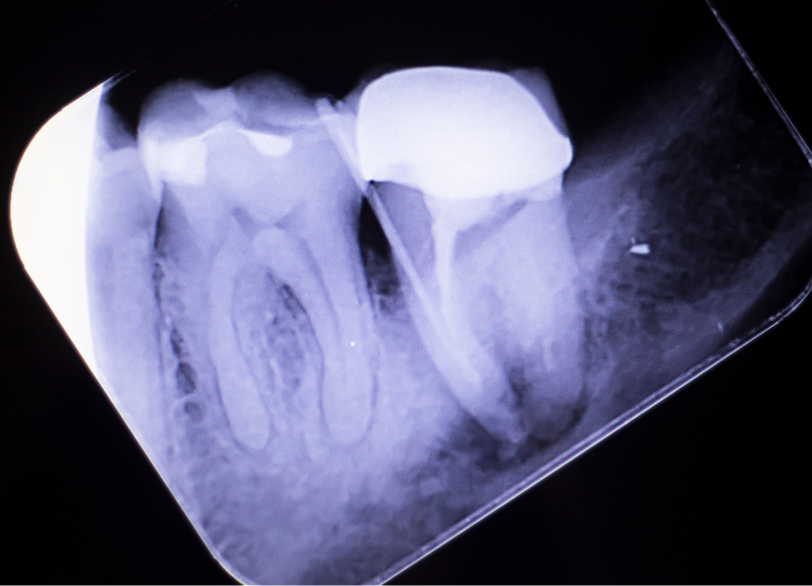

歯科用CTによる3次元診断

レントゲン写真は2次元の影絵であるため、根の重なりや、骨の裏側の病巣などは正確には分かりません。

当院では、治療前に歯科用CTを撮影し、歯根の形態や病巣の広がりを3次元(立体)画像で確認します。

「根が何本あるのか」「どの方向に曲がっているのか」を事前に把握することで、迷いのない安全な治療計画を立てることができます。